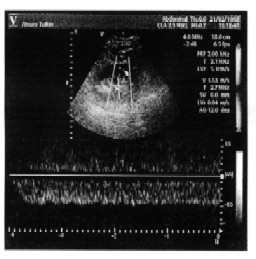

Рисунок 22. Динамика изменений кровотока в почечной вене:

а - до выполнения бхуджангасаны,

б - во время выполнения позы,

в - после завершения упражнения.

К сожалению, литературные данные об оттоке крови от почек весьма скудны. Описывается появление турбулентного потока в почечной вене при ее компрессии после трансплантации почки (Yang C. W. et al. 1996). В работах, посвященных синдрому сдавления левой почечной вены верхней брыжеечной артерией и брюшной аортой (Nutcracker syndrome), выявлено некоторое уменьшение пиковой скорости венозного оттока в воротах почки и резкое ускорение кровотока по вене в месте ее компрессии. О минимальной скорости оттока крови от почки не сообщается (Stavros A. T. et al. 1994, Kim S. H. et al. 1996). Поэтому мы обратились к собственным наблюдениям, примеры которых приведены выше. Монофазный венозный отток был обнаружен нами при проведении пробы с произвольной задержкой мочи у больных хроническим пиелонефритом, страдающих мочеточниково-лоханочным рефлюксом (рис. 18), у лиц с гидронефрозом (рис. 19), у пациента с острой задержкой мочи вследствие неопластического процесса в малом тазу (рис. 20), при поражении почек на фоне имеющегося цирроза печени (рис. 21). Основываясь на накопленных данных, мы осмеливаемся предположить, что патологические процессы, приводящие к повышенному обжатию вен в почке, способствуют формированию или с резко сниженными колебаниями или полностью монофазного венозного оттока. Причем этот параметр изменяется ранее наступления изменений в артериальном русле, свидетельствующих о большой тяжести изменений в почках. Воздействие позы "кобры", как мы считаем, происходит в пределах физиологических колебаний трансмурального давления на внутри - и внепочечные сосуды. Более чувствительными к такому "мягкому" воздействию естественно оказываются вены почки.

Следуя логике наших предыдущих исследований, мы провели изучение влияния позы "кобры" на венозный отток от почек при исходно нарушенном кровообращении в них. Во время отбора лиц, пригодных для нашей работы, у одного из инструкторов по йогическим упражнениям с большим стажем был выявлен измененный монофазный кровоток в почечной вене. Изменения были односторонними. Проба с позой "кобры" была отчетливо положительной (полное восстановление пульсирующего характера кровотока после позы). Рассмотрение повторных допплерограмм венозного кровотока спустя 3 месяца целенаправленных занятий практикой бхуджангасаны (поза "кобра") (рис. 22) свидетельствует, что исходный кровоток стал пульсирующим, во время принятия позы "кобры" он превращается в монофазный (что свидетельствует о хорошей технике исполнения позы), а после упражнения – его пульсации отчетливо возрастают. Единичные пока наблюдения в этом роде позволяют надеяться на положительное лечебное воздействие бхуджангасаны (позы "кобры") на отток крови по почечным венам.